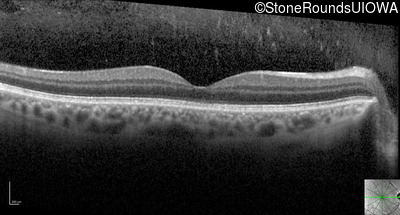

Optical Coherence Tomography - Right - 20/30 sc

Exemplar / OCT Stack

OCT Stack